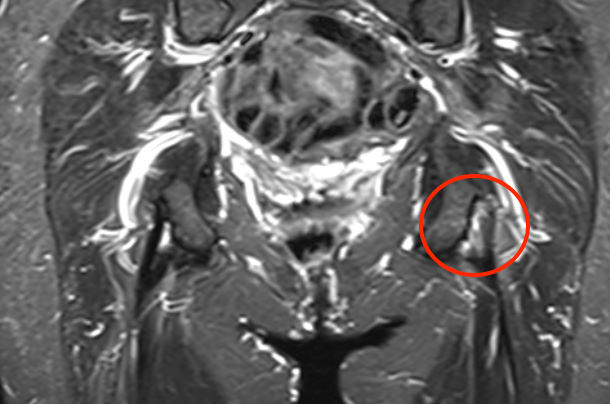

MRI

Peritendinous edema / low grade partial tears / tendinopathy

High grade partial tears